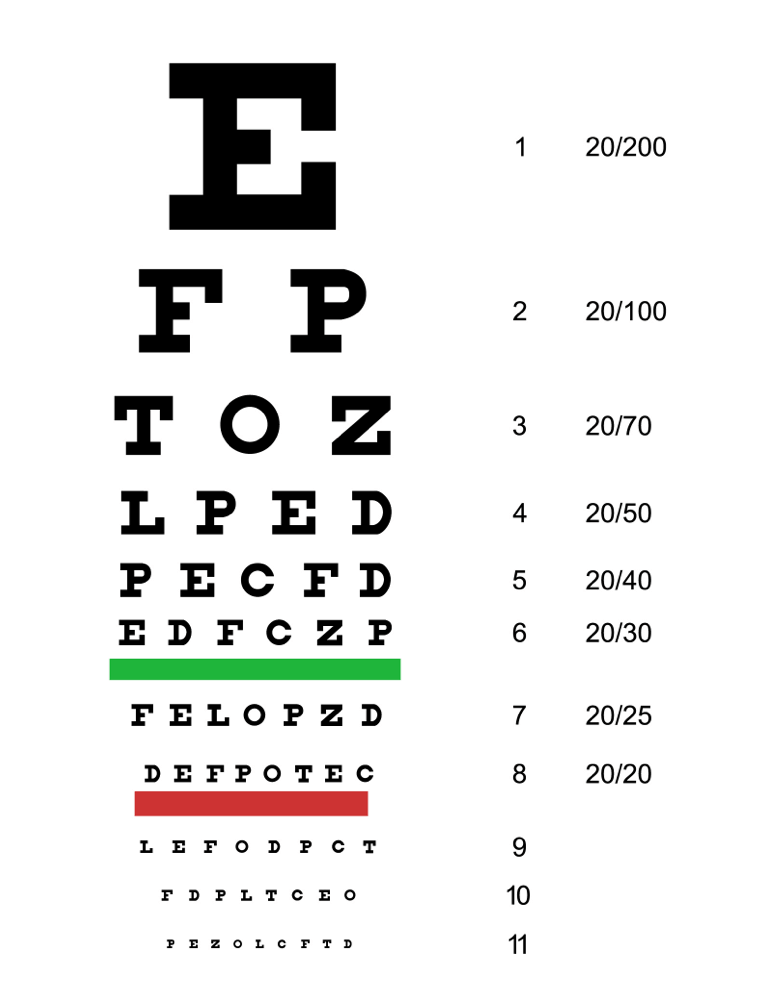

El principal síntoma que experimentan las personas con DMAE es la pérdida de visión. Por lo tanto, la DMAE suele diagnosticarse mediante un examen ocular rutinario. Un examen completo de agudeza visual mide la capacidad de una persona para ver detalles, formas y letras a una determinada distancia.3 La agudeza visual mejor corregida se evalúa normalmente utilizando una tabla de Snellen, pero tenga en cuenta que su profesional sanitario también puede utilizar otras tablas. El número de letras que una persona puede identificar correctamente representa su agudeza visual. Dicho de otro modo, cuanto más abajo en la tabla de Snellen pueda leer una persona, mejor será su agudeza visual.3